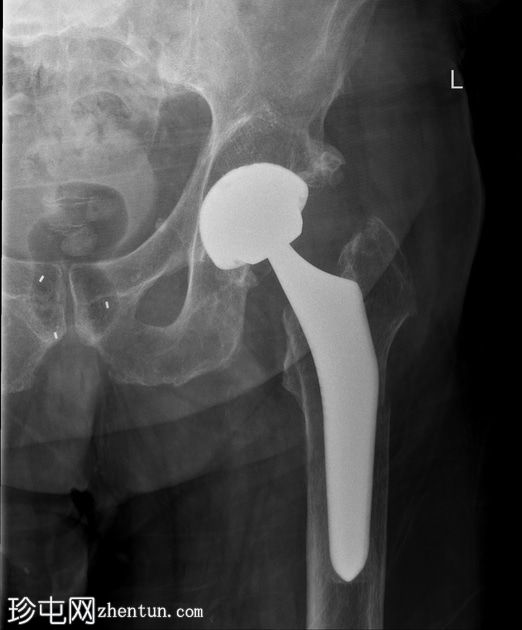

X光片

正面

可见左髋关节假体。左侧股骨近端存在轻微移位的假体周围骨折。